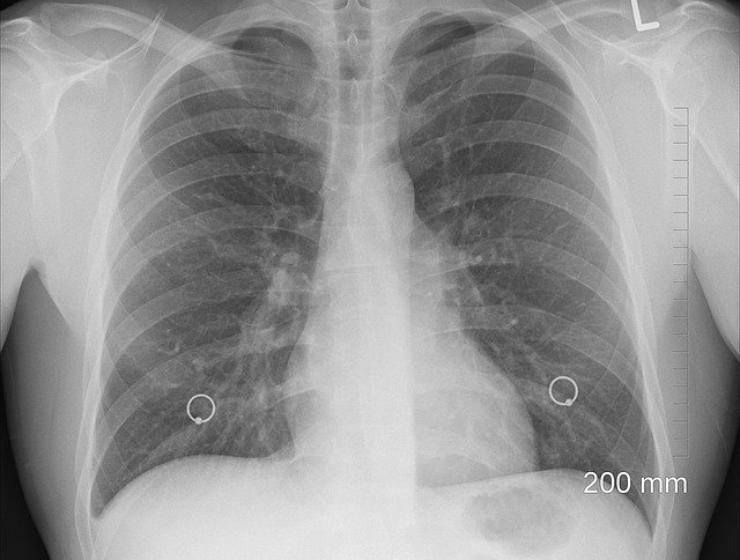

A questo punto entra in gioco il sistema immunitario. Qualora non riuscisse a respingere il Covid-19, si incorrerebbe il serio rischio di aggressione ai polmoni, che causa la polmonite. In alcuni casi (in particolar modo quando si hanno già patologie pregresse) si può sviluppare la sindrome da stress respiratorio acuta, dove i livelli di ossigeno nel sangue crollano e la respirazione diventa difficoltosa. Ciò può portare addirittura al decesso.

Stando sempre a quanto affermato dalla ricerca pubblicata da Science, questo processo può essere guidato da una iperreazione del sistema immunitario denominata “tempesta di chitochine”, ovvero le molecole che guidano la risposta immunitaria sana, ma che facendolo oltre il necessario attaccano anche le cellule sane. Le conseguenze sono delle perdite dei vasi sanguigni, calo della pressione sanguigna e coagulazione che può sfociare in un collasso dell’organo.

Dunque non solo polmoni, vengono attaccati anche i vasi sanguigni e cuore. Ciò spiega anche perché coloro che avevano pregresse patologie cardiovascolari sono più a rischio, come ad esempio ipertensione e diabete. A Brescia una donna ricoverata con sintomi da infarto è stata poi trovata positiva. Il quadro purtroppo non è completo. A rischio anche l’intestino ricco dei recettori Ace2, quelli presenti anche nel naso. Possono essere danneggiati anche fegato, reni e cervello. In tal senso si sono registrati casi di encefaliti, crisi epilettiche, perdita di coscienza ed ictus nei soggetti affetti dal coronavirus.